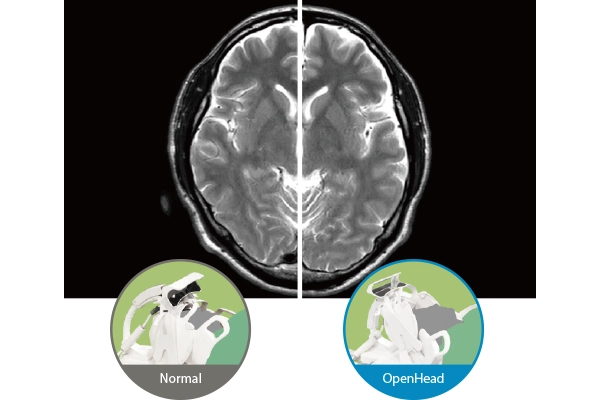

“OpenHead Mode“ which allows imaging without covering the anterior side of the coil over the patient’s face is equipped. By not obstructing the patient’s field of vision, this mode helps reduce the psychological stress associated with the imaging process.